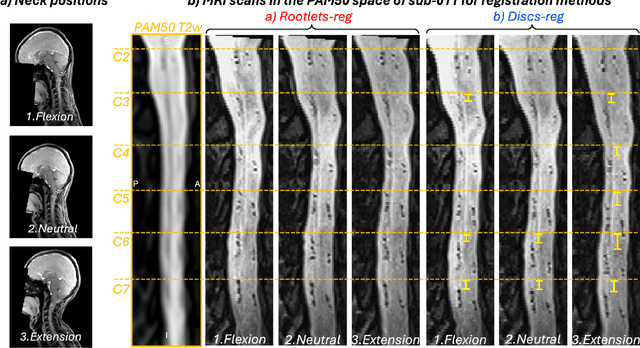

Abstract:Spinal cord functional MRI studies require precise localization of spinal levels for reliable voxelwise group analyses. Traditional template-based registration of the spinal cord uses intervertebral discs for alignment. However, substantial anatomical variability across individuals exists between vertebral and spinal levels. This study proposes a novel registration approach that leverages spinal nerve rootlets to improve alignment accuracy and reproducibility across individuals. We developed a registration method leveraging dorsal cervical rootlets segmentation and aligning them non-linearly with the PAM50 spinal cord template. Validation was performed on a multi-subject, multi-site dataset (n=267, 44 sites) and a multi-subject dataset with various neck positions (n=10, 3 sessions). We further validated the method on task-based functional MRI (n=23) to compare group-level activation maps using rootlet-based registration to traditional disc-based methods. Rootlet-based registration showed superior alignment across individuals compared to the traditional disc-based method. Notably, rootlet positions were more stable across neck positions. Group-level analysis of task-based functional MRI using rootlet-based increased Z scores and activation cluster size compared to disc-based registration (number of active voxels from 3292 to 7978). Rootlet-based registration enhances both inter- and intra-subject anatomical alignment and yields better spatial normalization for group-level fMRI analyses. Our findings highlight the potential of rootlet-based registration to improve the precision and reliability of spinal cord neuroimaging group analysis.